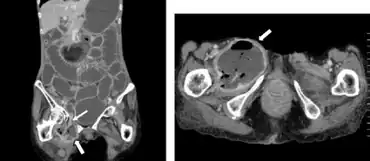

| Computed tomography revealed a right obturator hernia arrow and abscess spreading to right thigh | |

An obturator hernia is a rare type of hernia of the pelvic floor in which pelvic or abdominal contents protrudes through the obturator foramen. Because of differences in anatomy, it is much more common in women, especially multiparous and older women who have recently lost much weight. The diagnosis is often made intraoperatively after presenting with bowel obstruction.